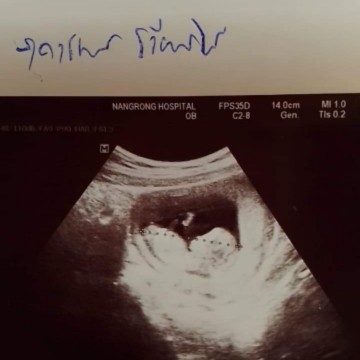

น้อง12สัปดาห์แล้วค่ะน้องจะเริ่มมีเเขนขาแล้วรึยังคะ

บ้านนี้ซาวไปตอน10+5วีค น้องมีครบแล้วคะ แขน ขา หัวใจดวงน้อยๆเต้นด้วย